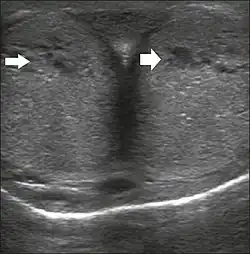

Transverse ultrasound image, ventral view of the penis. Image obtained after induction of an erection, 15 min after injection of prostaglandin E1, showing dilated sinusoids (arrows).[48]

Penile ultrasonography with doppler can be used to examine the erect penis. Most cases of ED of organic causes are related to changes in blood flow in the corpora cavernosa, represented by occlusive artery disease (in which less blood is allowed to enter the penis), most often of atherosclerotic origin, or due to failure of the veno-occlusive mechanism (in which too much blood circulates back out of the penis). Before the Doppler sonogram, the penis should be examined in B mode, in order to identify possible tumors, fibrotic plaques, calcifications, or hematomas, and to evaluate the appearance of the cavernous arteries, which can be tortuous or atheromatous.[48]

Erection can be induced by injecting 10–20 μg of prostaglandin E1, with evaluations of the arterial flow every five minutes for 25–30 min (see image). The use of prostaglandin E1 is contraindicated in patients with predisposition to priapism (e.g., those with sickle cell anemia), anatomical deformity of the penis, or penile implants. Phentolamine (2 mg) is often added. Visual and tactile stimulation produces better results. Some authors recommend the use of sildenafil by mouth to replace the injectable drugs in cases of contraindications, although the efficacy of such medication is controversial.[48]

Before the injection of the chosen drug, the flow pattern is monophasic, with low systolic velocities and an absence of diastolic flow. After injection, systolic and diastolic peak velocities should increase, decreasing progressively with vein occlusion and becoming negative when the penis becomes rigid (see image below). The reference values vary across studies, ranging from > 25 cm/s to > 35 cm/s. Values above 35 cm/s indicate the absence of arterial disease, values below 25 cm/s indicate arterial insufficiency, and values of 25–35 cm/s are indeterminate because they are less specific (see image below). The data obtained should be correlated with the degree of erection observed. If the peak systolic velocities are normal, the final diastolic velocities should be evaluated, those above 5 cm/s being associated with venogenic ED.[48]